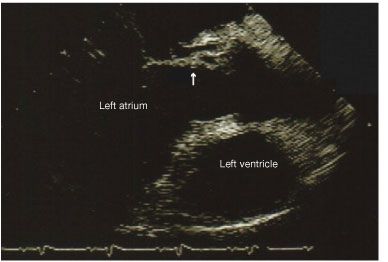

The blood cultures remained positive for 4 days despite appropriate antibiotic therapy. A transthoracic echocardiogram (TTE) showed no valvular vegetations. A subsequent transesophageal echocardiogram (TEE) revealed no vegetations, an abscess in the region of the aortic annulus, an abnormal communication between the aorta and left atrium consistent with sinus of Valsalva fistula and aneurysm (Figure), and an additional communication between the right coronary cusp and right atrium.

Figure –This echocardiogram shows abnormal communication between the aorta and left atrium, suggesting a sinus of Valsalva fistula and an aneurysm.